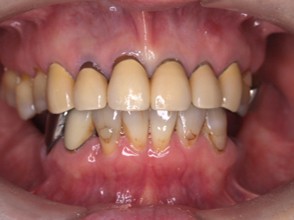

歯周病組織再生療法・インプラント・セラミック治療の症例紹介(三隅歯科クリニック)

症例詳細

| 主訴 | 60代女性 他院で義歯を作ったが噛みにくい、バネを掛けている左下の銀歯が何度も取れる、しっかり噛めるようになりたい |

| 治療内容 | 歯周病組織再生療法、インプラント治療、セラミック治療を行いました。 |

| 治療費 | 4,000,000円(税込み) |

| 治療期間 | 1年半 |

| 治療回数 | 25回 |

| 想定されたリスク | 失活歯が多く、太くて長い土台がすでに入っていたので、歯根破折のリスクがあった |